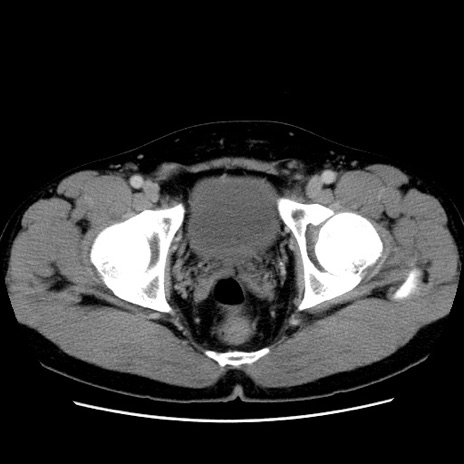

症例4(横断像)

【症例】30歳代男性

【主訴】腹痛、嘔吐

【現病歴】昨晩から突然の腹痛あり、その後嘔吐、軟便も出現。腹痛が改善しないため救急搬送となる。2日前にしめ鯖の食事歴あり。

【身体所見】意識清明、苦悶様、BP 135/90mmHg、BT 35.7℃、腹部:平坦、やや硬、心窩部〜臍部に自発痛、圧痛あり、筋性防御+、反跳痛-

【データ】WBC 8100、CRP 0.57